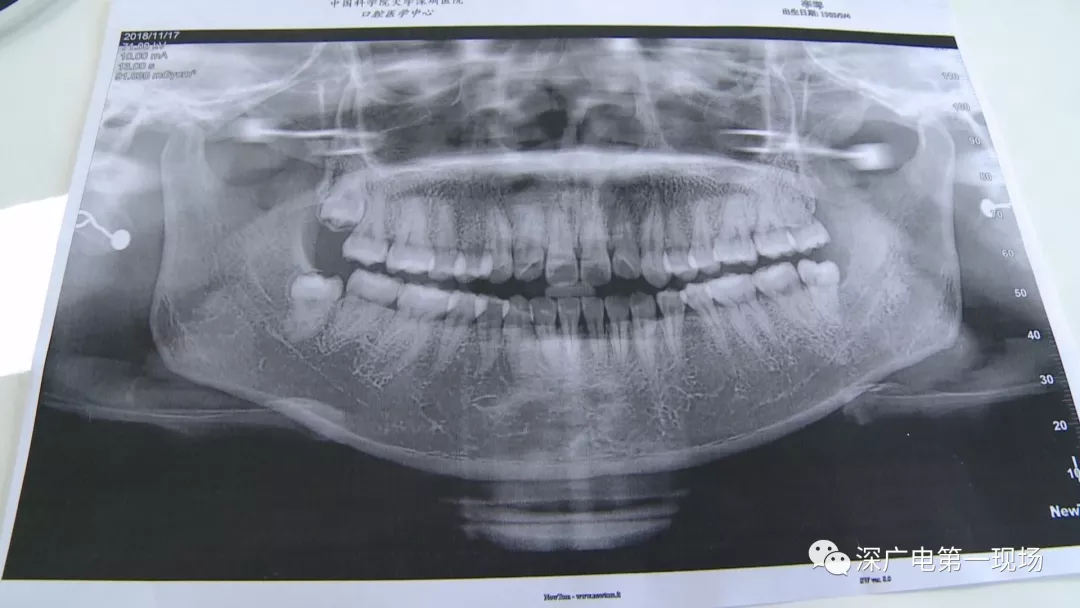

复杂牙拔出程序较复杂

针对李女士的情况,医生介绍,当时要想拔出李女士的这颗智齿,难度还是很大的,属于复杂智齿的拔除术。她的风险在于距离神经管近,同时这颗牙齿完全埋在牙床最后的位置,直接往外拔,会加大颌骨的风险,因此需要先切开,让牙齿暴露后,切小再慢慢地拔出。